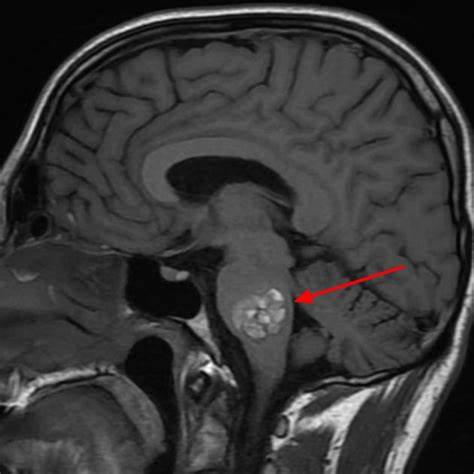

脑海绵状血管瘤,有必要手术吗?为了诊断对于海绵状血管瘤,主要使用磁共振成像,其中这些病变显示典型的“爆米花”外观,低信号周围有晕圈。我们...

脑海绵状血管瘤或 海绵状脑血管瘤 ,这是一种血管畸形,可以出现在大脑的不同区域,在脊髓中少见。脑海绵状血管瘤由不规则血管形成的黑莓形血管球...

脑海绵状血管瘤无症状或者偶然发现,需要手术吗?脑海绵状血管瘤常会因非特异性或无关症状而做影像学检查时被发现(图1)。对于无症状的脑干海绵状血...